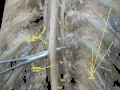

![]() The spinal cord shown in yellow extends through most of the length of the vertebral column to connect the brain with peripheral nerves. | |